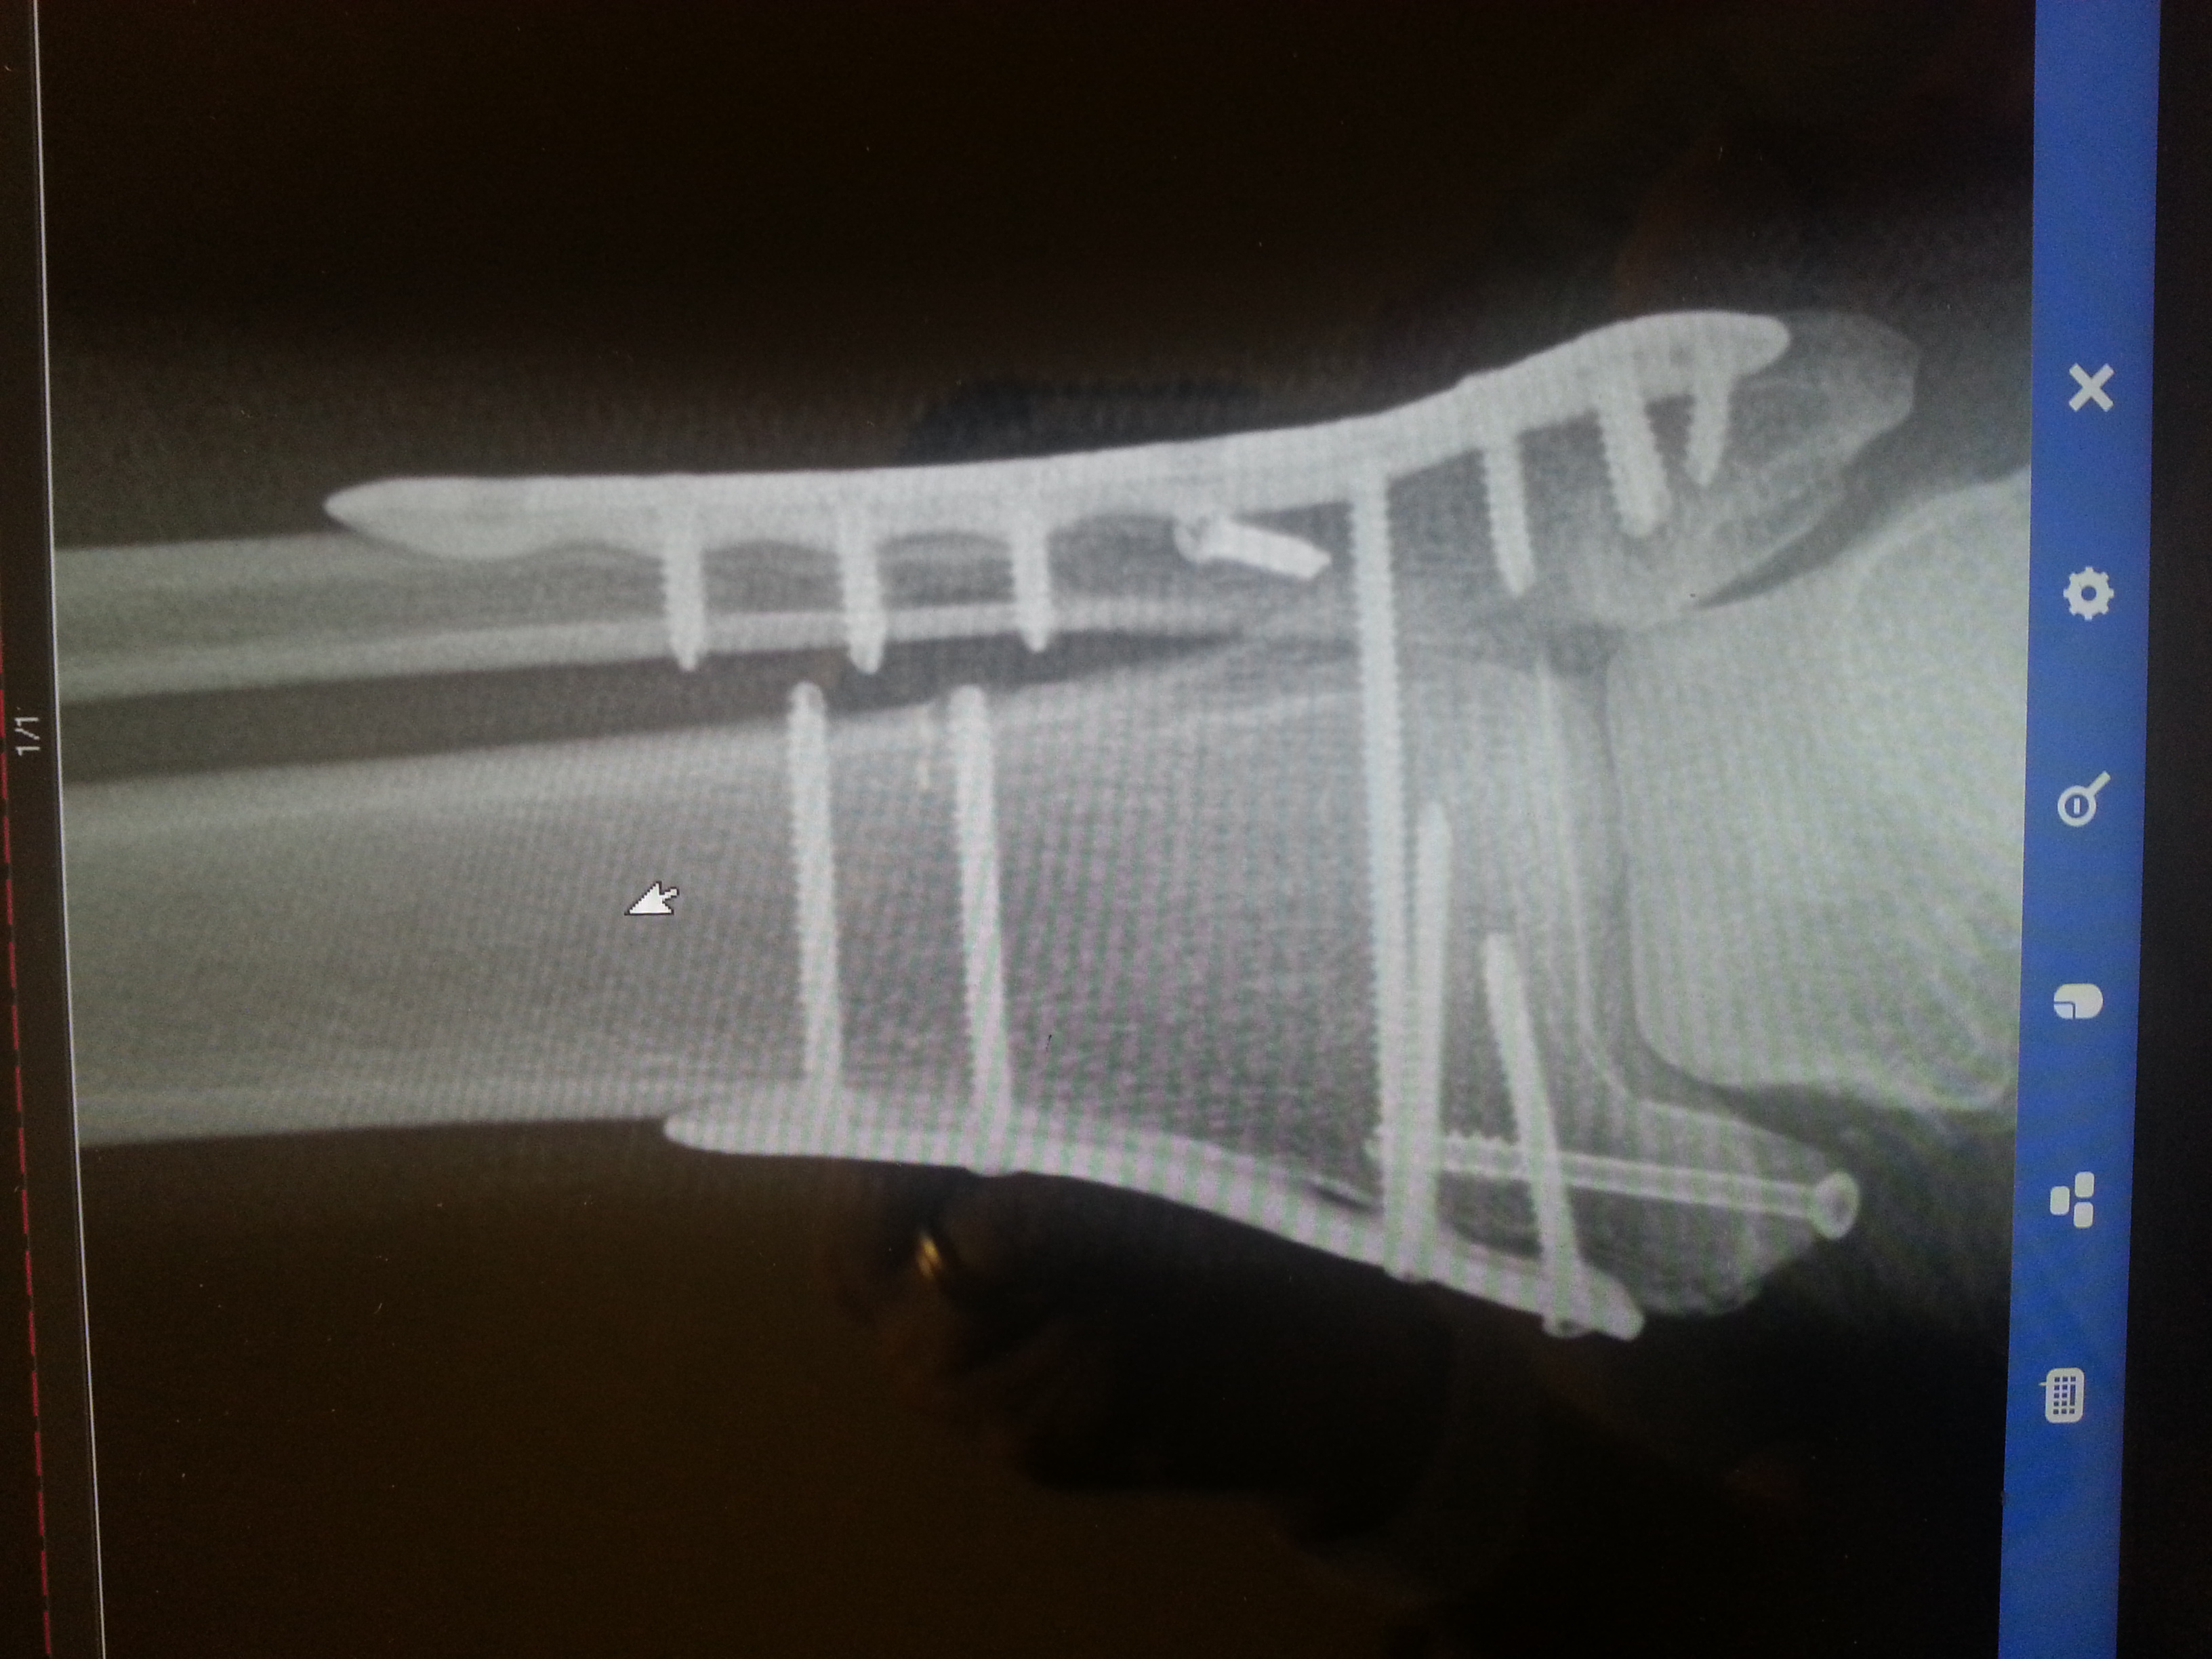

Ankle surgery, a couple of titanium plates one one each side and some screws in the front.

I thought you had a screw loose, but it looks like all 13 are tight! That's quite a bit of hardware my friend.

Well this is what my foot looks like 10 days after my surgery.